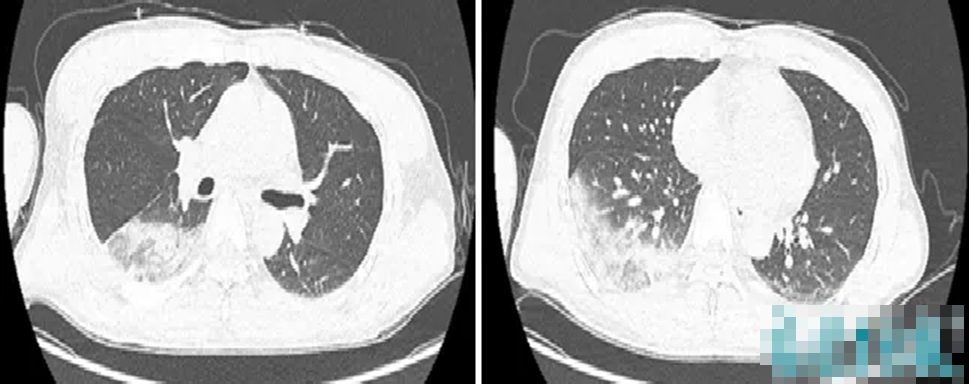

Sau khi uống rượu cùng nhau, 6 người đàn ông nhập viện trong tình trạng co giật, hôn mê, ngừng thở. Chiều 19-10, Bệnh viện Đa khoa Thanh Chương (Nghệ An), cho biết bệnh viện...